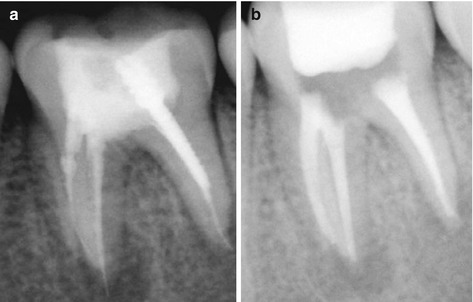

January 4, 2026 Service 0 Waa maxay dhuux daawayntu(Root Canal Treatment)? Dhuux daawayntu waa hab lagu daweeyo iligga marka uu suusku ama jabniinku gaadho dhuuxa ama neerfaha iligga kusoo jira. Sidoo kale kolka uu iliggu infection sameeyo.